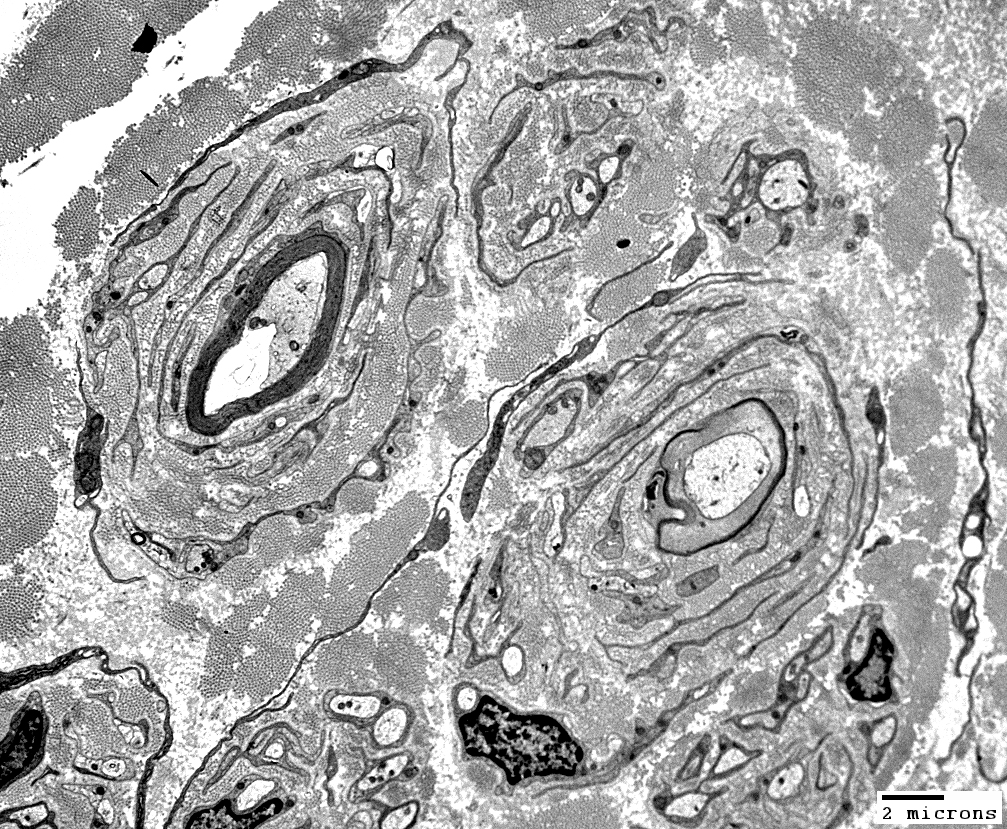

Onion Bulbs: Ultrastructure

CIDP, Childhood onset

From: Robert Schmidt MD

|

Onion bulbs, Large: Several layers surround thinly myelinated axons

Layers include

Schwann cell processes

Schwann cell basal lamina

Connective tissue

Outer rim: My be fibroblast process

Central axon: Thinly myelinated

Onion Bulbs: Around thinly myelinated axons